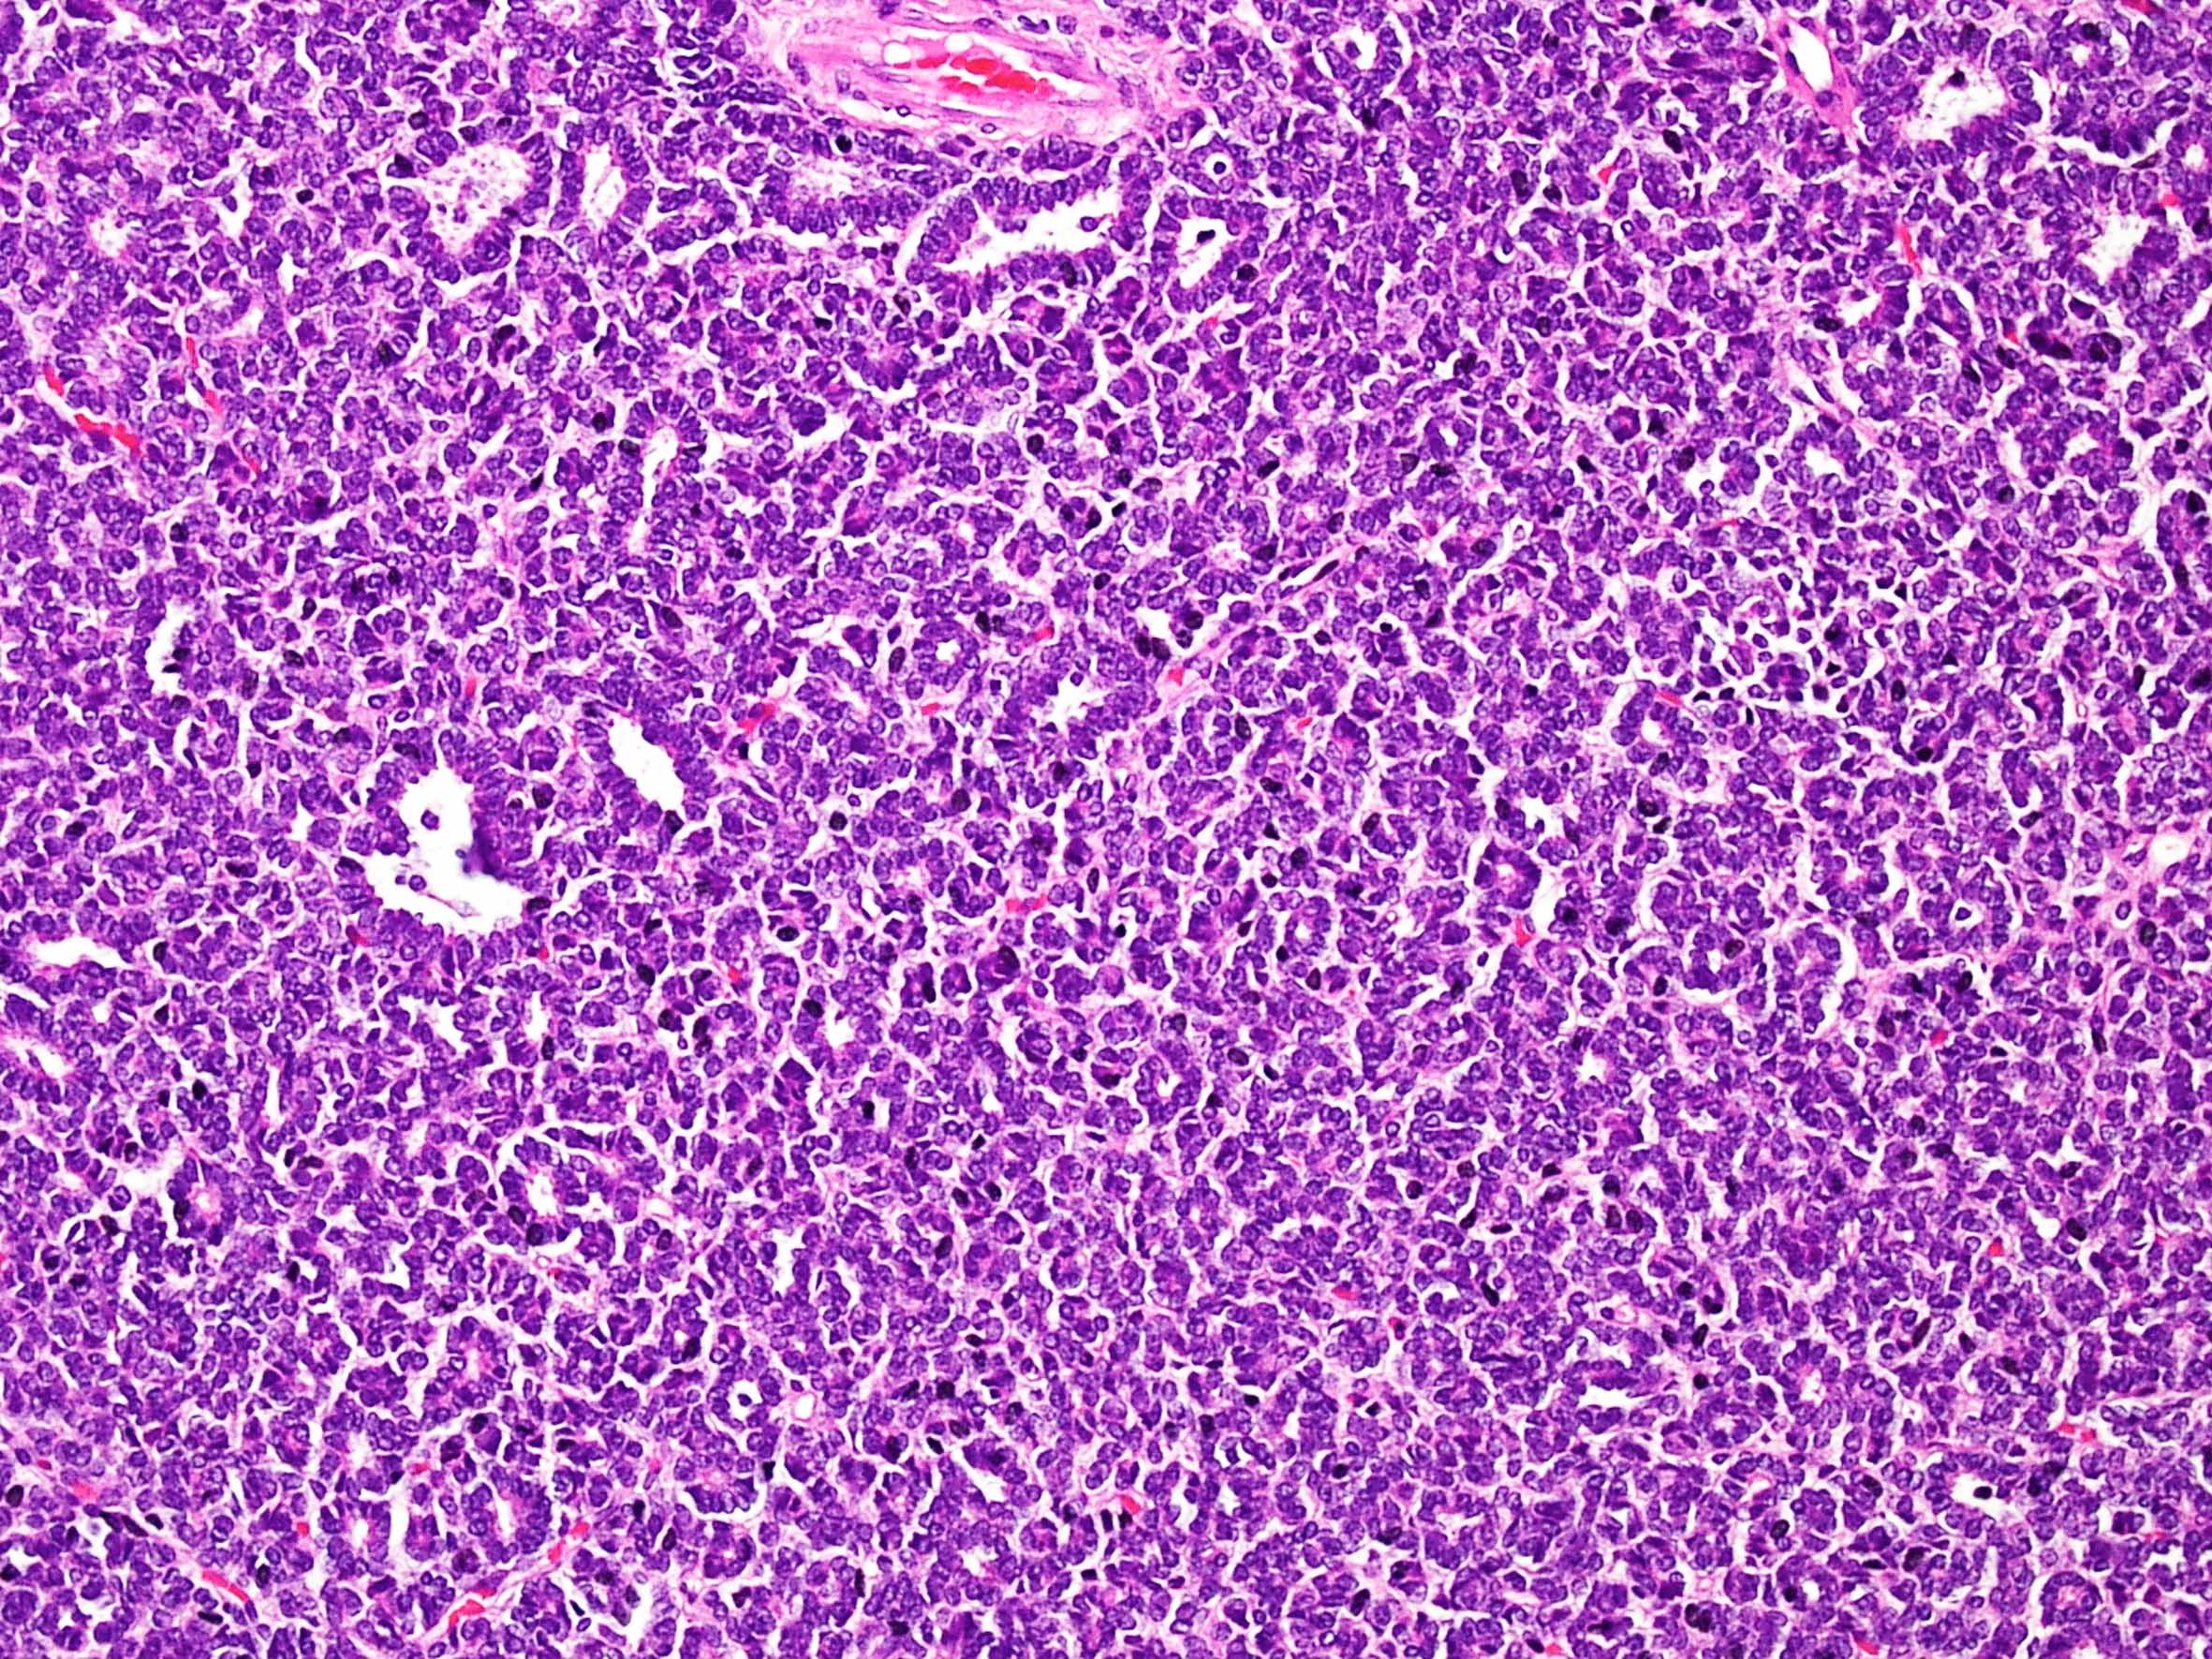

Case description (by case creator):

Metanephric adenoma